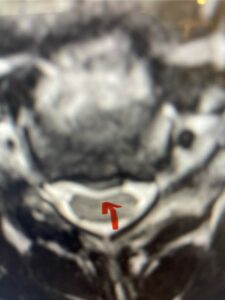

In this next case, this patient is a 47 year-old female who presents with intractable low back pain with severe pain, numbness, and weakness in the right lower extremity that had gotten progressively worse over a year. The patient had failed conservative management including physical therapy and epidurals. She was noted to have ⅘ weakness of plantar flexion. MRI demonstrated a large right L5-S1 disc herniation with severe compression of the descending right S1 nerve root (Fig 3). It was decided to perform a right L5-S1 hemilaminectomy for removal of the disc fragment and decompress the S1 nerve root. When you expose the disc, one must be certain to release any anterior adhesions to the nerve root in order to prevent a dural tear during retraction of the nerve root. It is also important to make sure during exposure and you finally encounter the dura after removing the ligamentum and fat, to make sure you are looking at the nerve root and not the main trunk of the thecal sac because if you don’t you can avulse or damage the nerve root if you retract the wrong structure.

Fig. 3a: Sagittal and axial T2-weighted lumbar MRI images demonstrating large right L5-S1 disc herniation (red arrows)